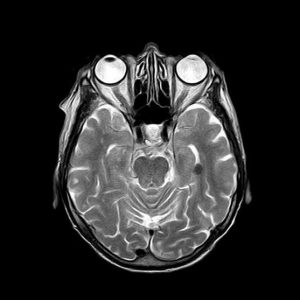

Para cada técnica de imágenes médicas, hay algoritmos especializados, ya que las características de las imágenes son diferentes, y su interpretación también. Por ejemplo, las imágenes de tomografía axial computarizada (TAC) pueden parecerse a las imágenes de resonancia magnética, sin embargo, la información que contienen es muy diferente, como se muestra a continuación.

Imágenes de TAC: se generan empleando rayos x y las formas e intensidades que se observan están relacionadas con la morfología y propiedades físicas de las estructuras anatómicas.

Imágenes de Resonancia: se crean a partir de campos magnéticos y contienen información relacionada con la actividad metabólica y el funcionamiento de los órganos y tejidos.

examen resonancia magnetica tac de cerebro examen resonancia magnetica tac de cerebro 2

Izquierda: imagen de resonancia magnética del cerebro. Derecha, TAC del cerebro